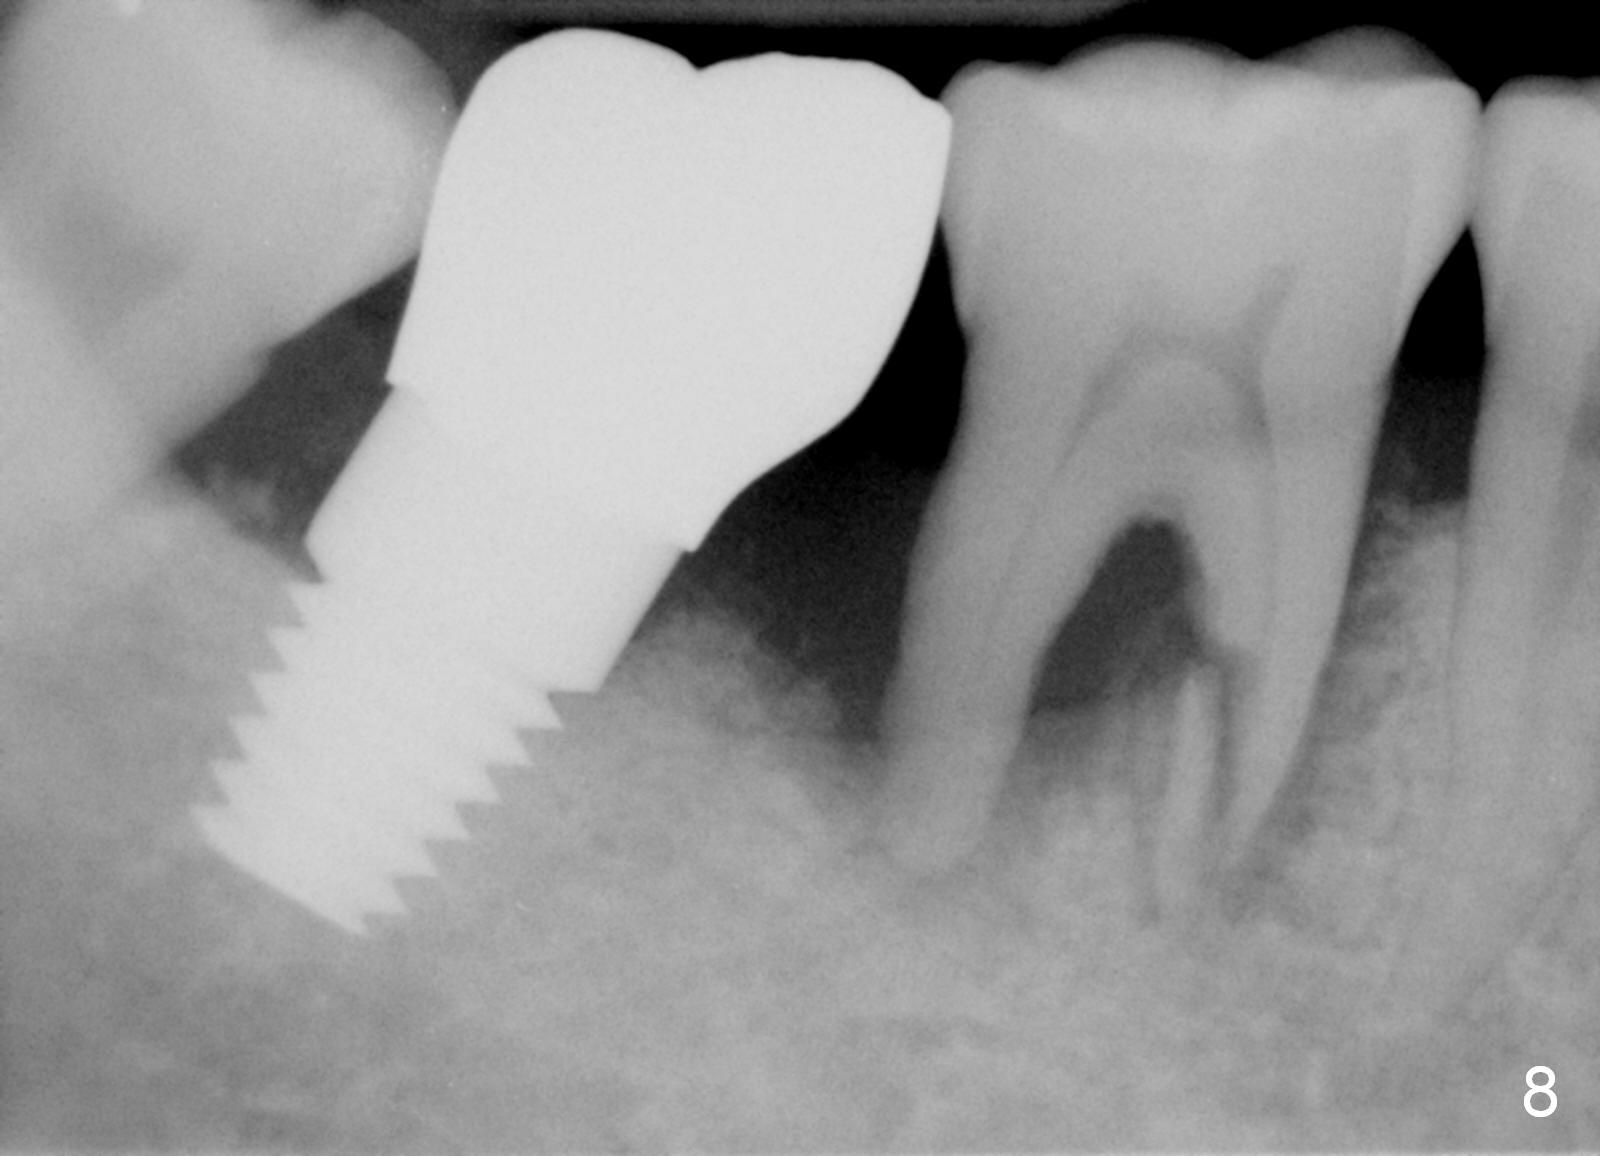

Luckily the patient returns for #31 implantation 4 months post socket preservation. Bone forms in the alveolus and above (Fig.1 black and white arrowheads, respectively). A 6 mm tissue punch is used to open the wound (Fig.2). Osteotomy forms using bone expanders, reamers and taps (Fig.3: 6x14 mm tap). Without infection, local anesthesia is more easily achieved than immediate implant when infection exists. The depth is controlled more readily with delayed implantation. Following adjustment of trajectory, a 7x11 mm implant is placed with insertion torque 60 Ncm (Fig.4 I). Fig.5 shows that the implant obliterates the wound; an abutment (A) is placed to retain perio dressing. With formation of new bone from socket preservation, insertion torque seems to be more easily obtained with the short implant. There is no space to re-use the harvested bone (Fig.6). The implant remains stable postop. Apparent new bone is forming toward the distal coronal threads 5 months postop (Fig.7). The bone around the implant remains stable 17 months post cementation (Fig.8), although there is an episode infection at the neighboring tooth (#30). The patient is more eager to have implants for the maxilla, since the flipper has lost. After implant placement at #7, the pain at #30 becomes more severe.